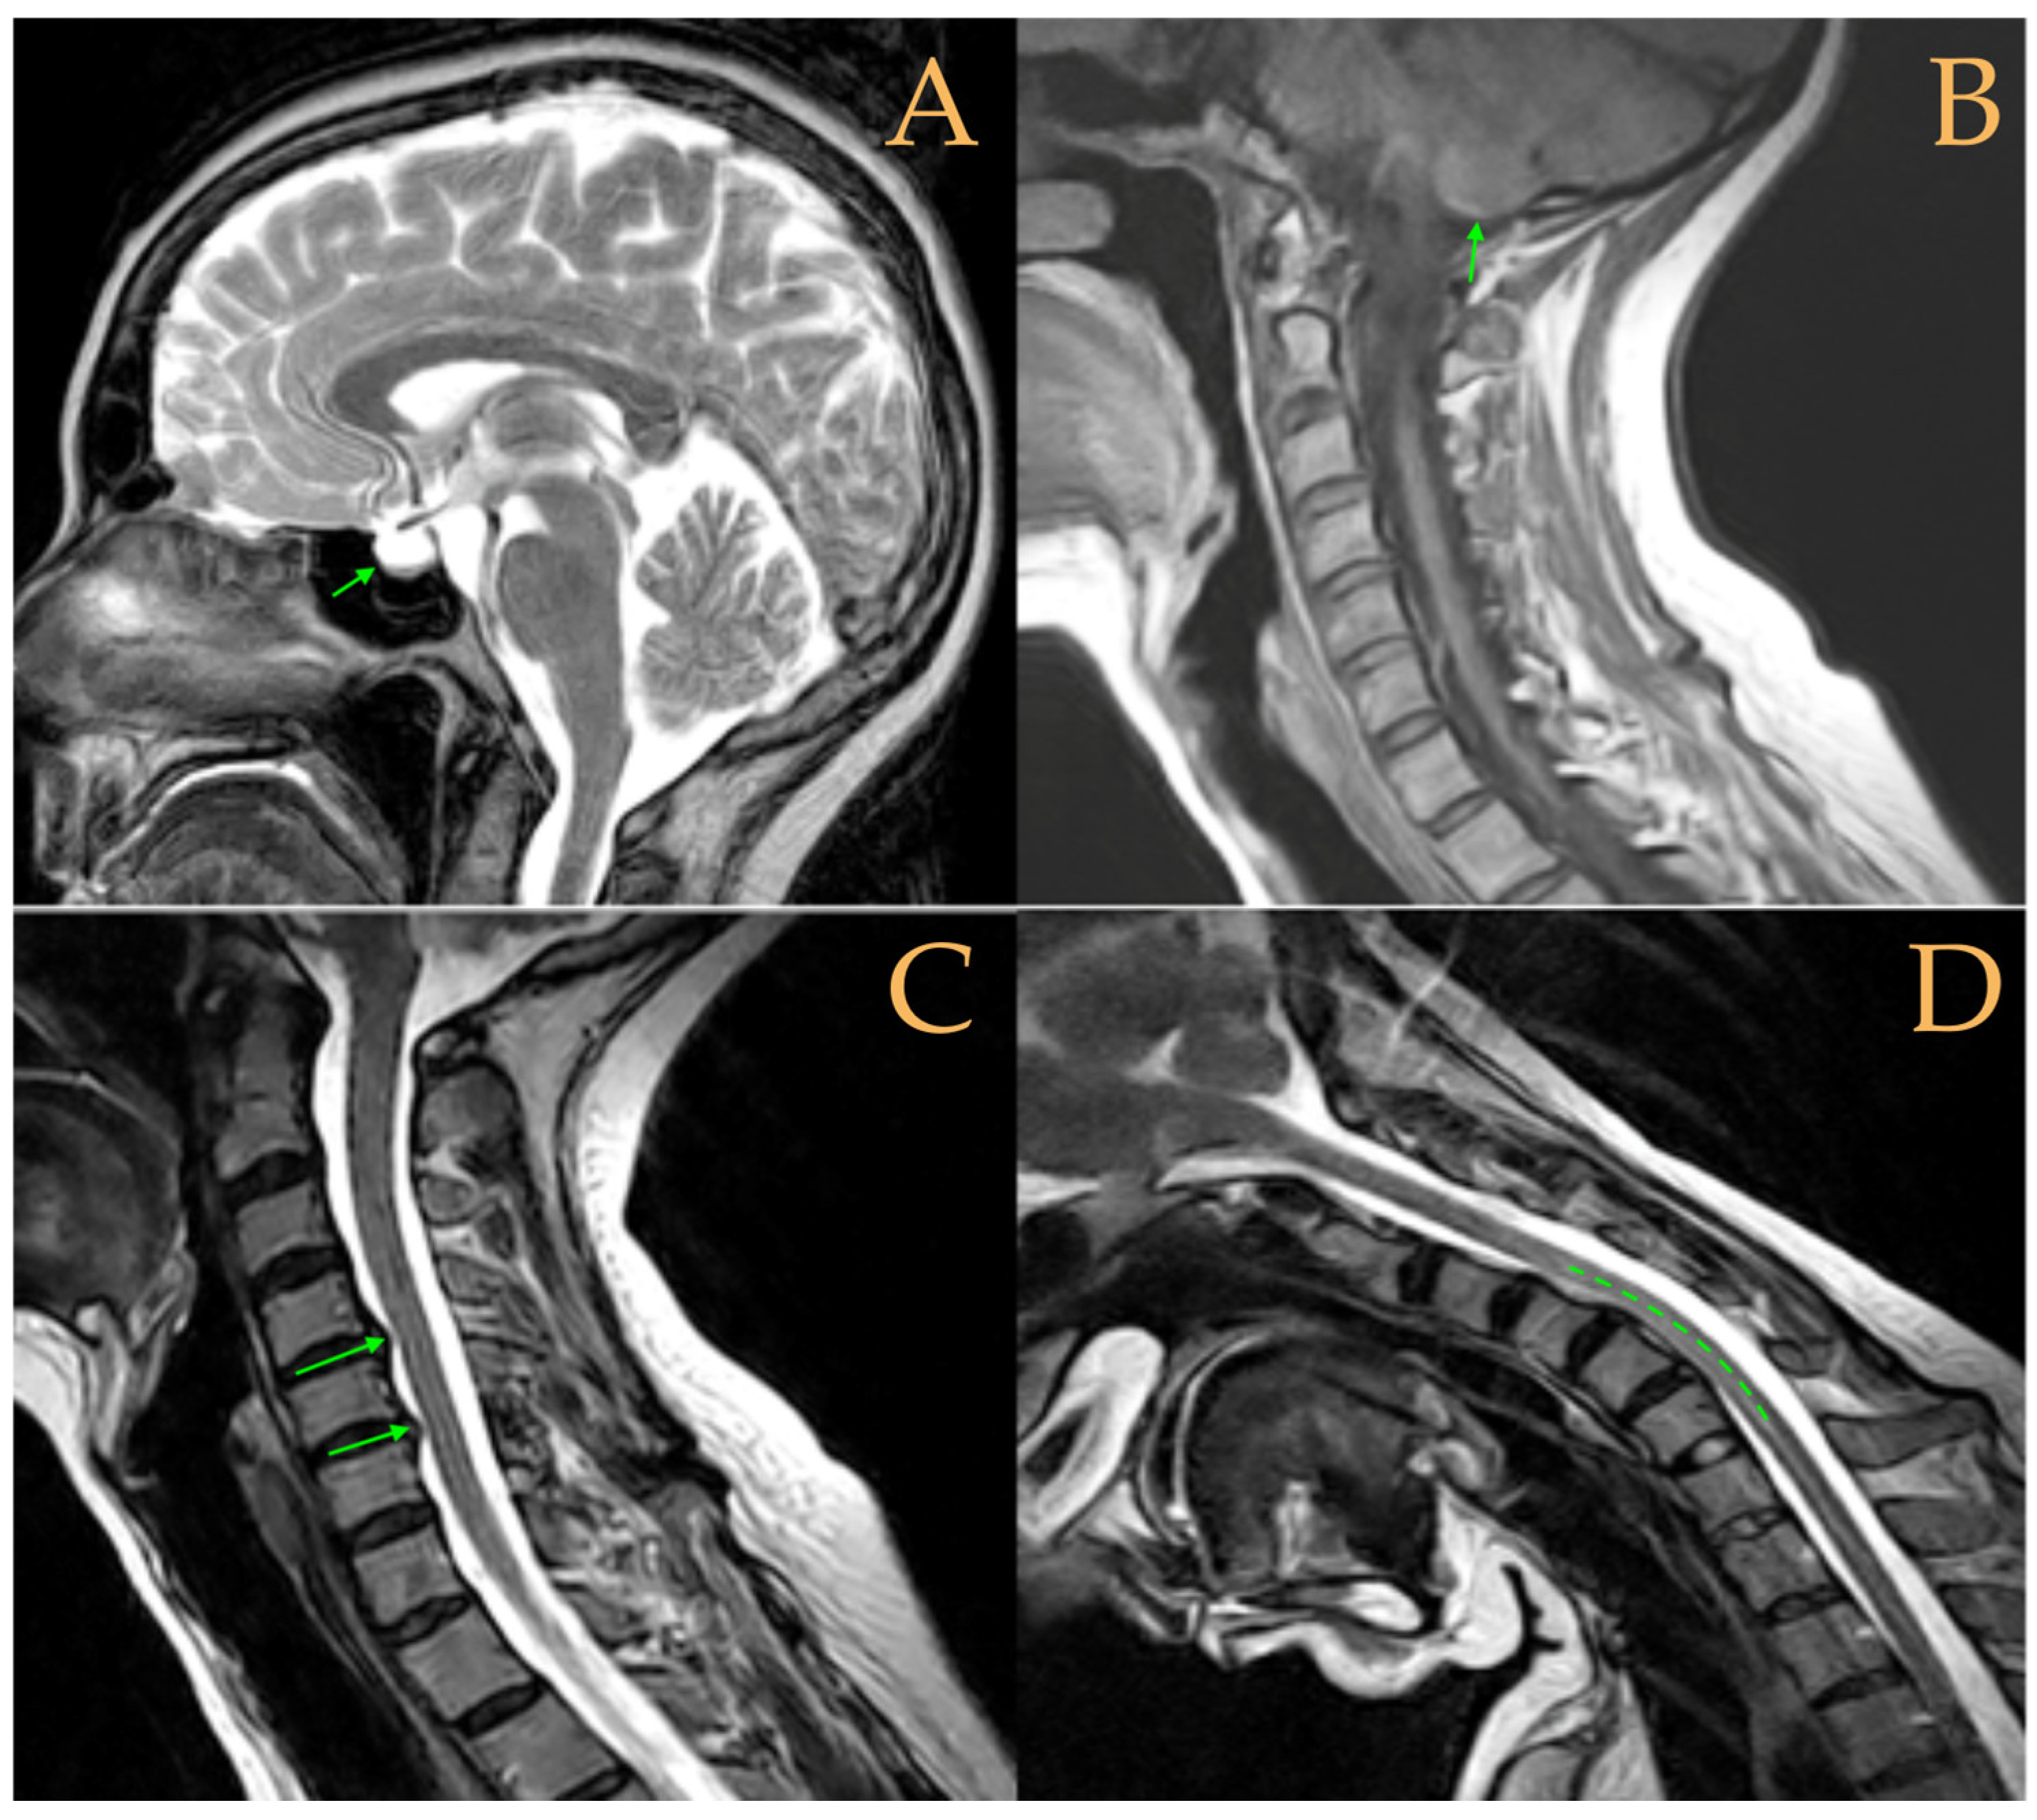

Magnetic resonance imaging showed a slight descent of the cerebellar tonsils, multiple diseased discs, and conus medullaris at the level of the middle third of the L1 vertebra. The X-ray images of the entire spine revealed a mild dextroconvex thoraco-lumbar scoliosis with 5° Cobb angle (Figure 1).

Figure 1. Imaging of patient 1. A: Mild descent of the cerebellar tonsils (arrows); B: multiple disc disease (arrows) and straightening of the cervical spine (interrupted line); C: conus medullaris at the middle third of L1 (arrow); and D: mild deviation of the vertebral column (interrupted lines).